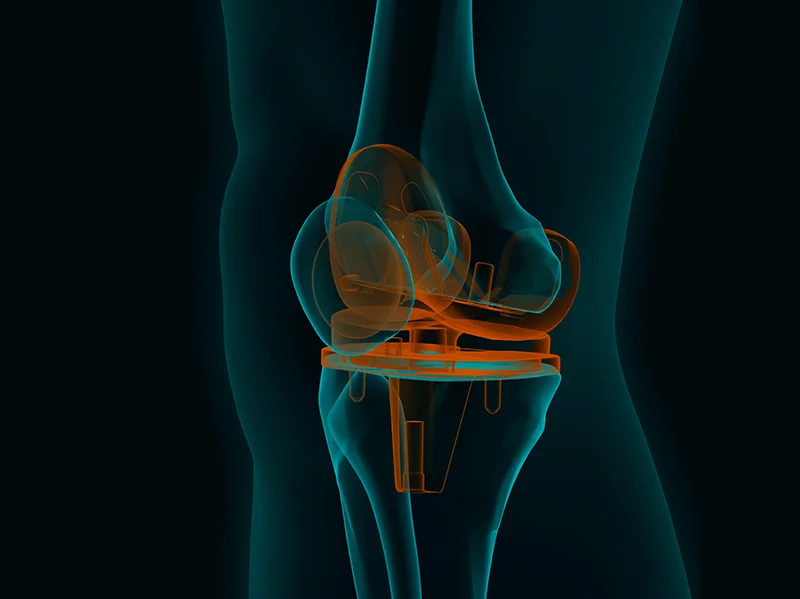

Representative image for total knee replacement procedure.

The image shows a 3D rendering of the total knee prosthesis in place.